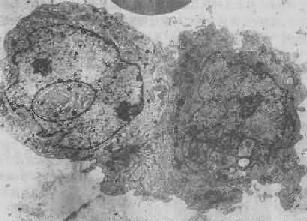

图1-2 细胞核染色质边集中毒性肝炎的肝细胞×8000

图1-3 核内假包含体

垂体嗜酸性细胞瘤的瘤细胞,左侧瘤细胞核内可见一卵圆形包含体,有膜包绕,内含细胞器和胞浆分泌颗粒×8400